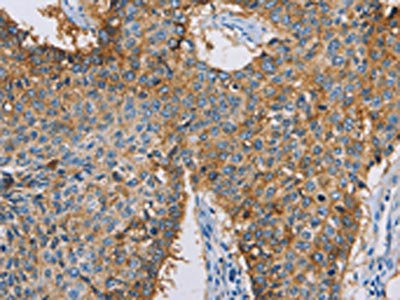

The image on the left is immunohistochemistry of paraffin-embedded Human lung cancer tissue using CSB-PA251431(CDCP1 Antibody) at dilution 1/50, on the right is treated with synthetic peptide. (Original magnification: ×200)

The image on the left is immunohistochemistry of paraffin-embedded Human thyroid cancer tissue using CSB-PA251431(CDCP1 Antibody) at dilution 1/50, on the right is treated with synthetic peptide. (Original magnification: ×200)